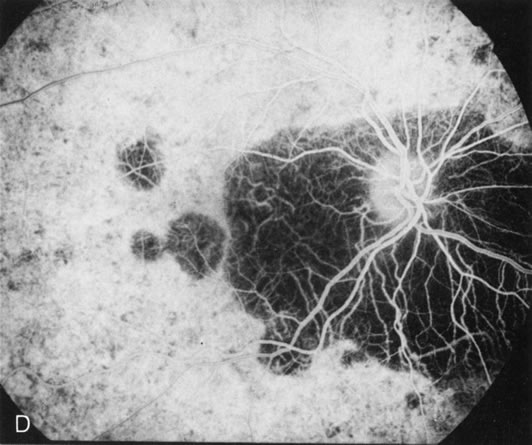

Fig. 4. Choroideremia and choroideremia carrier. A. The choroidal atrophy in this affected male is not apparent in the fundus. B. However, the angiogram shows diffuse atrophy of the choriocapillaris with persistent visualization of the larger choroidal vessels. C. This carrier female has peripapillary choroidal atrophy and diffuse pigment mottling. D. The patchy areas of focal choroidal atrophy that occasionally occurs in carriers is evident on angiography.

The typical carrier female, with focal or diffuse pigment mottling, does not show choroidal atrophy. However, a few carrier females have a more severe form with focal areas of choroidal atrophy. The presence of these areas, and possible progression, can be documented by FA (Fig. 4C and D). These carriers exhibit a mosaicism, which is explained by the Lyon hypothesis of random X-chromosome inactivation.